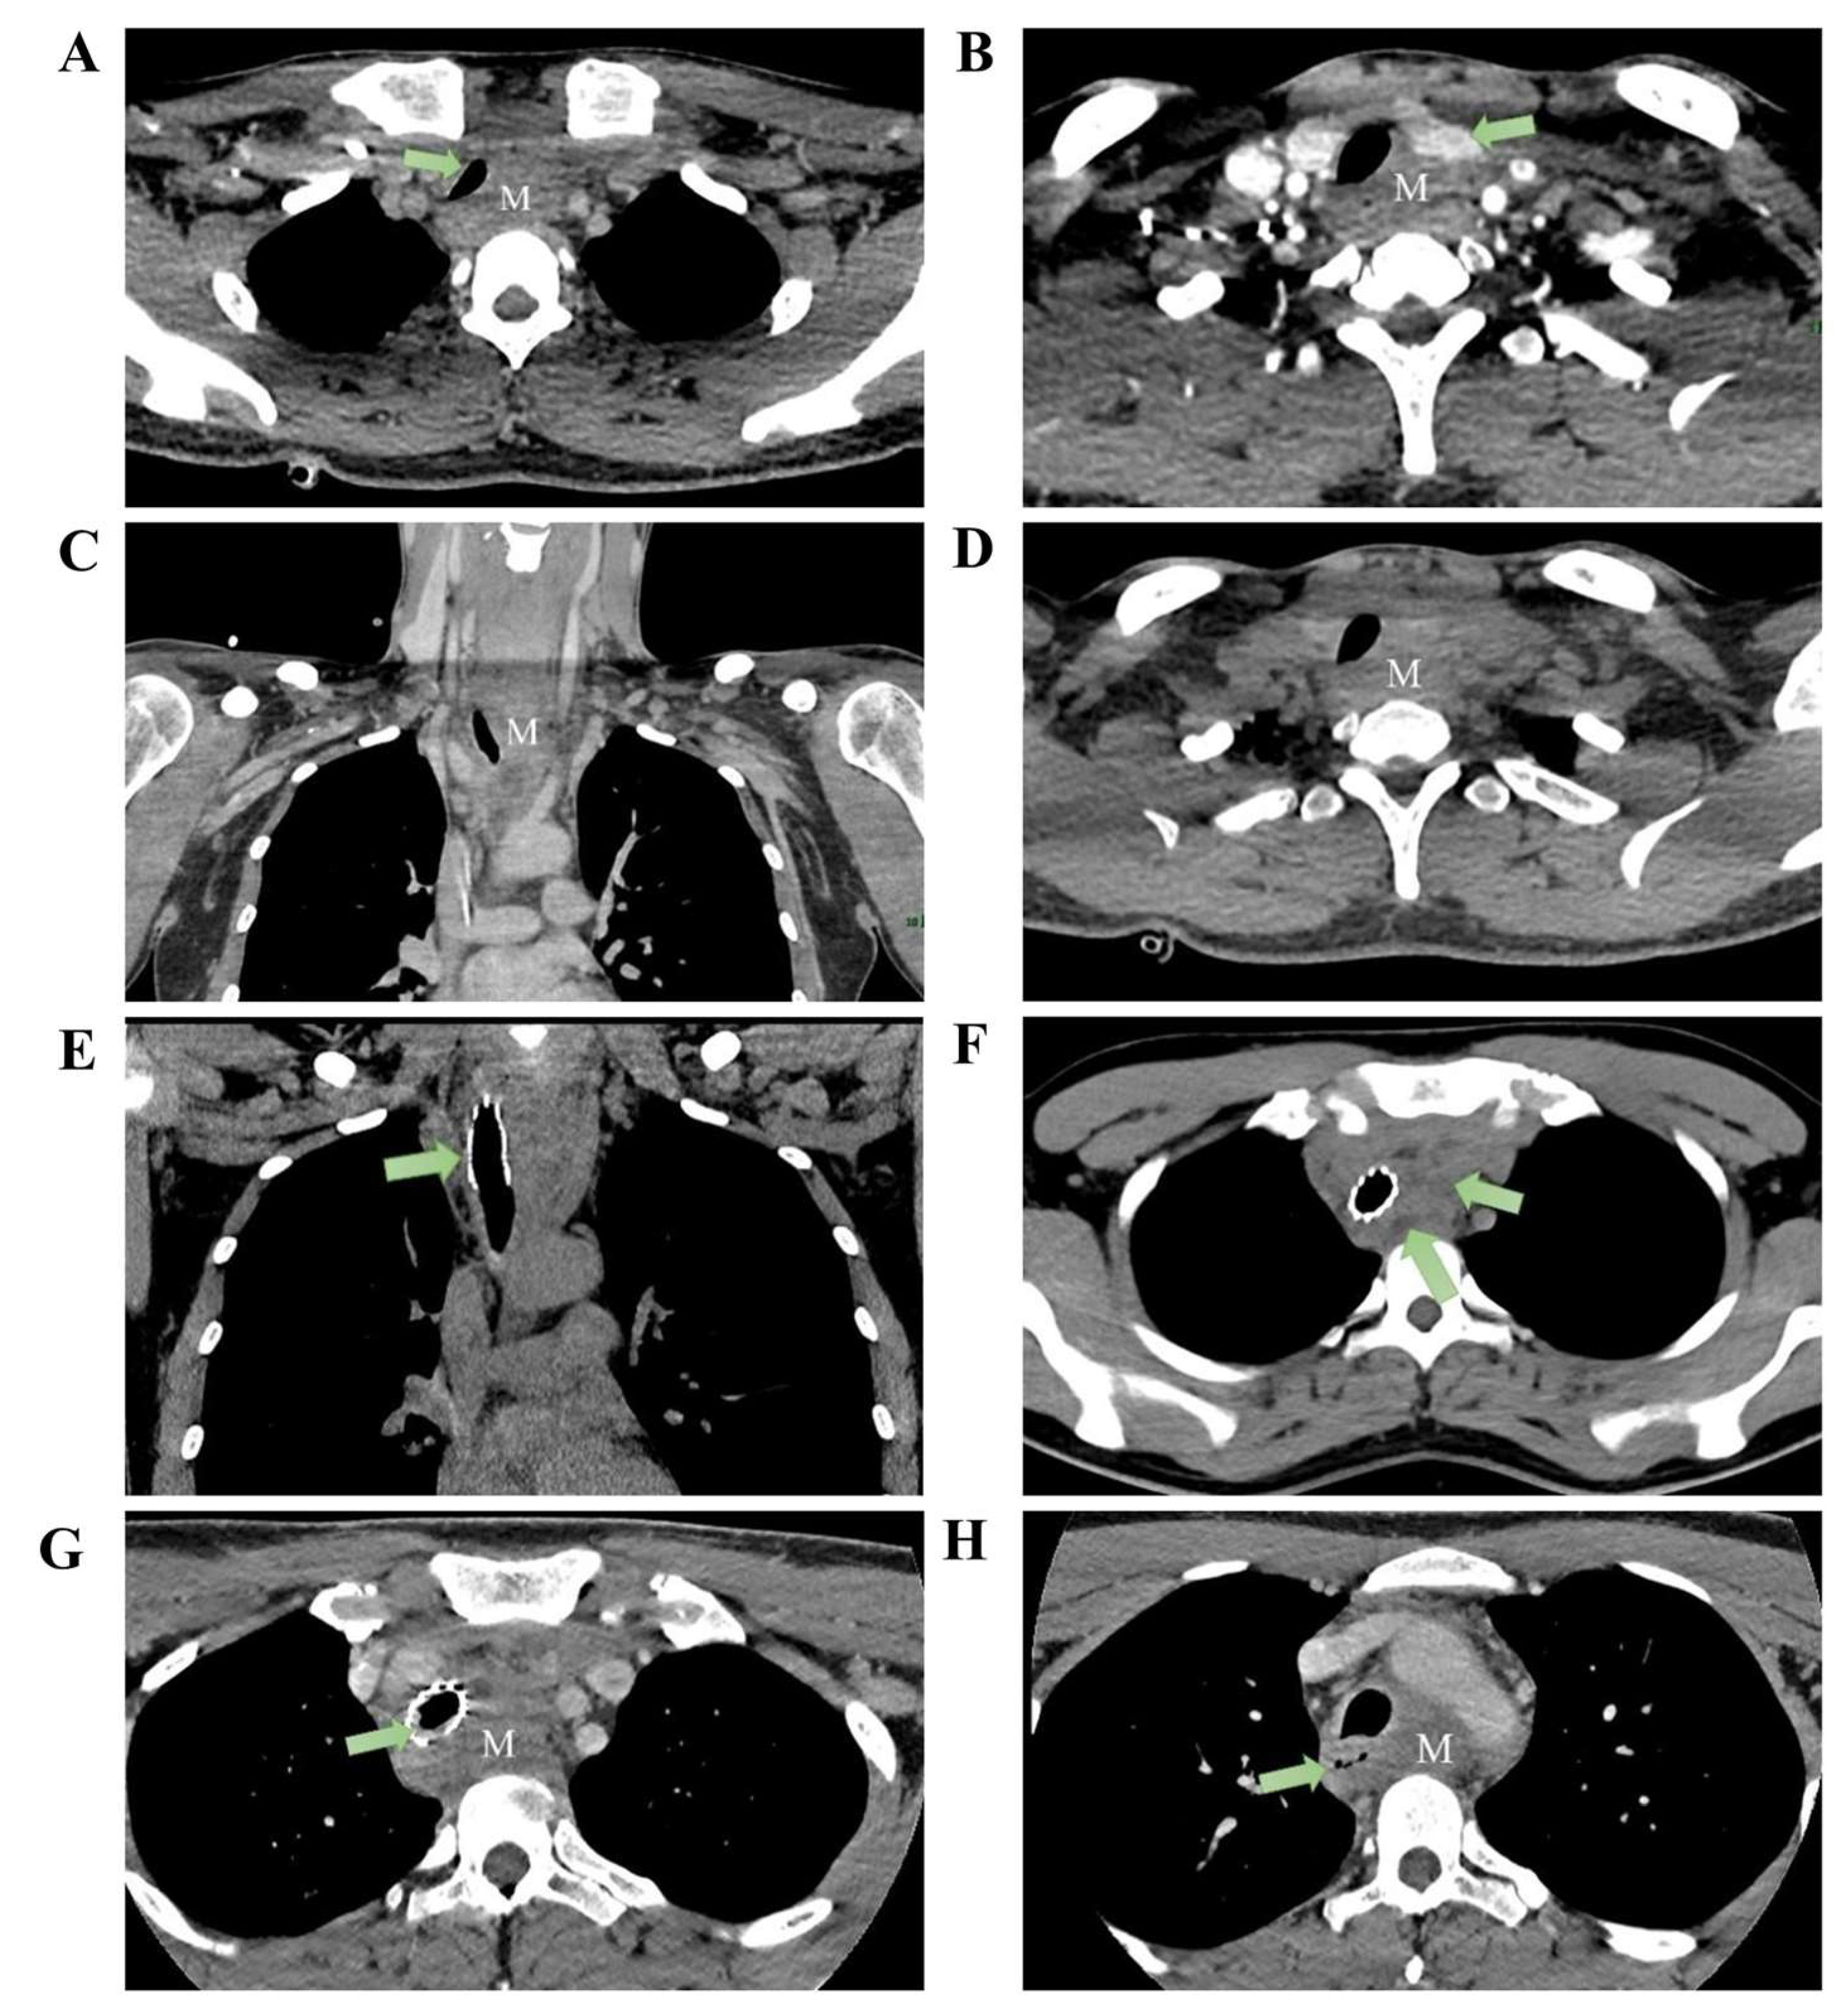

A 28-year-old construction worker presented with a seven-month history of progressive dyspnea. He reported occupational dust exposure but denied smoking or alcohol consumption. His body mass index (BMI) was 22.5 kg/m2. Past medical history, family history, and drug allergies were unremarkable. Upon admission, physical examination revealed significant hypoxia and tachycardia: SpO2 80%, respiratory rate 33 breaths/min, heart rate 115 bpm, blood pressure 122/73 mmHg, and temperature 36.2 °C. Lung auscultation revealed bilateral wheezing without focal neurological or cardiovascular deficits. Baseline laboratory evaluations, including blood cell counts, C-reactive protein (CRP), erythrocyte sedimentation rate (ESR), and renal and liver function tests, were within normal limits. Tumor markers, including CEA and CA19-9, were negative. Arterial blood gas analysis (performed on high-flow oxygen, FiO2 58%) showed a PaO2 of 133 mmHg and PaCO2 of 45 mmHg. Spirometry revealed an FEV1/FVC ratio of 69.4%. Contrast-enhanced CT demonstrated circumferential soft-tissue thickening surrounding the proximal esophagus (3.9 × 2.3 cm; longitudinal extent: ~10 cm), causing esophageal narrowing and persistent tracheal compression. No mediastinal lymphadenopathy, pleural abnormalities, or chest-wall invasion were observed (Figure 1).

Figure 1.

Pre-treatment imaging: CT reveals an anterior superior mediastinal mass (measuring approximately 3.9 × 2.3 cm) with the following features: (A) tracheal compression, (B) compression of the left thyroid lobe, (C) heterogeneous enhancement of the mass in the venous phase coronal section, and (D) axial plain CT scan shows no cystic changes within the lesion. Post tracheal stent placement: (E) CT coronal section demonstrates stent placement within the trachea. (F) Mass shows scattered cystic changes within its parenchyma. Two months post-treatment: (G) Mass demonstrates significant enlargement, measuring approximately 5.5 × 2.7 cm, with intraluminal granulation tissue hyperplasia observed within the tracheal stent. (H) Esophageal compression evident (M: mass).

Given impending airway obstruction, 3-D CT of the tracheobronchial tree confirmed upper-tracheal stenosis with a ~3 cm narrowed segment. Emergency bronchoscopic balloon dilation and placement of a metallic stent were performed under general anesthesia using a supraglottic airway.

The balloon was inflated to 4.9 atm for 30 s (two cycles), followed by deployment of a partially covered metallic stent (40 mm × 16 mm) just below the vocal cords. The balloon was then inflated to 4.8 atm for 25 s (two cycles), and a second partially covered stent (40 mm × 16 mm) was deployed at the carina. Bronchoscopy demonstrated tumoral protrusion into the tracheal lumen with ~4 cm of stenosis. Forceps sampling was followed by two dilations and deployment of a 1.6 × 4.0 cm partially covered metallic stent (Figure 1E). Transbronchial needle aspiration, liquid-based cytology, and rapid on-site evaluation demonstrated only mild squamous epithelial atypia with scattered inflammatory cells and no malignant features. Dyspnea improved promptly after stenting. After symptomatic relief, upper gastrointestinal endoscopy identified a smooth-surfaced narrowing ~23 cm from the incisors, precluding adequate fine-needle aspiration. Considering the patient’s age, mass effect, and oncologic risk, the multidisciplinary team (MDT) recommended CT-guided percutaneous mediastinal biopsy. Histopathology demonstrated proliferative fibrosis with hyaline degeneration and chronic inflammatory infiltrates without malignancy. The patient declined further invasive procedures and was discharged.

Two months later, he re-presented with dysphagia and anterior-neck warmth and a self-limited low-grade fever (<38 °C) resolved with oral antibiotics. PET-CT showed SUVmax 4.6 at the mediastinal lesion with no uptake elsewhere (Supplementary Figure S1). CT confirmed a stable stent without restenosis, but the mass had enlarged to 5.5 × 2.7 cm with minimal/absent contrast enhancement (Figure 1G). PET-CT and bone-marrow assessment were unremarkable (Supplementary Figures S1 and S2), yet interval growth and location maintained concern for mediastinal lymphoma. A dual-guided strategy was employed, combining endoscopic ultrasound (EUS) with CT-guided percutaneous hollow-needle aspiration. EUS yielded limited material with few atypical cells. CT-guided sampling provided tissue in which histopathology established ectopic pancreatic tissue within fibrotic stroma with hyaline degeneration and chronic inflammation (Figure 2). Flow cytometry on the paired aspirate identified a small monoclonal mature B-cell population (CD20bright, CD22+, CD79a/b+, predominantly CD10−/CD5−) with κ-light-chain restriction (κ 92.96% vs. λ 5.63%; κ/λ ≈16.5) and a high Ki-67 proliferation index (~86% within the CD79b+ gate) (Figure 3), raising concern for a coexisting B-cell lymphoid process. However, no morphologic evidence of lymphoma was present on histology, precluding definitive subclassification. Metagenomic next-generation sequencing (mNGS) and routine laboratory tests did not identify infectious etiologies. Further staging and definitive treatment planning were constrained by the patient’s refusal of surgical excision or additional biopsy.